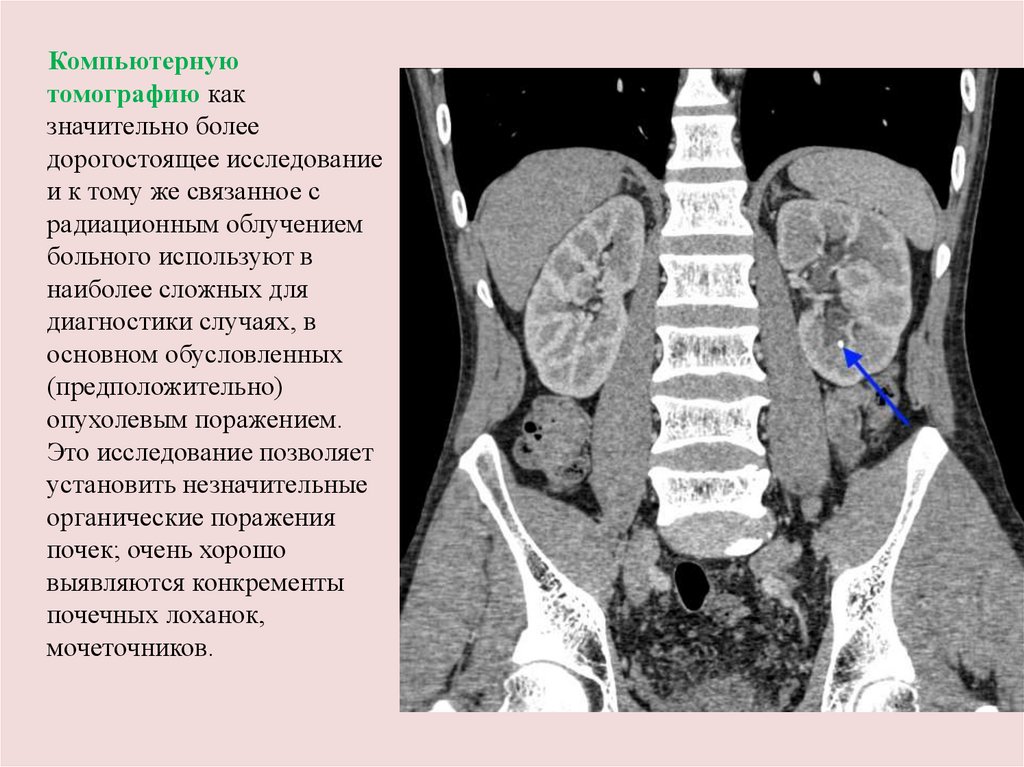

Компьютерную

томографию как

значительно более

дорогостоящее исследование

и к тому же связанное с

радиационным облучением

больного используют в

наиболее сложных для

диагностики случаях, в

основном обусловленных

(предположительно)

опухолевым поражением.

Это исследование позволяет

установить незначительные

органические поражения

почек; очень хорошо

выявляются конкременты

почечных лоханок,

мочеточников.